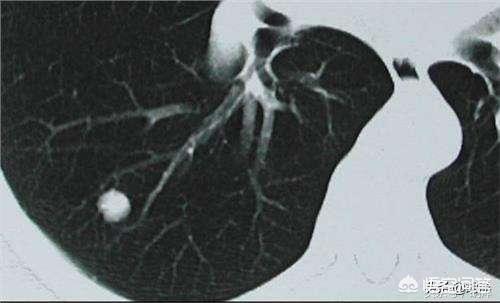

Lungenknoten sind kugelförmige Läsionen in der Lunge, die weniger als 3 cm groß sind. Mit dem weit verbreiteten Einsatz der Computertomographie der Brust bei medizinischen Untersuchungen wird die Entdeckungsrate von Lungenknoten immer höher, und viele Menschen haben sich auf Lungenknoten untersuchen lassen, ohne dass sie Beschwerden hatten, und sie haben Angst vor Lungenkrebs, wie es im Internet heißt, also wie groß sind die Knoten?

Lungenknoten werden je nach ihrer Dichte in verschiedene Typen eingeteilt: Knoten mit höherer Dichte, die auf dem CT der Brust als weiße Punkte erscheinen, werden als solide Knoten bezeichnet, während Schliffknoten eine geringere Dichte haben und wie Wasserdampf auf dem Glas aussehen. Glasschliffknötchen, insbesondere reine Glasschliffknötchen, sind in der Regel bösartiger.

Wir kennen diese Vorstellung von der Diagnose der Krankheit, und dann gehen wir zurück zum Kopf, um über Lungenknoten zu sprechen. Lungenknoten sind runde oder unregelmäßige Läsionen mit einem Durchmesser von höchstens 3 cm in der Lunge, die in der Bildgebung als Schatten mit erhöhter Dichte erscheinen, die homogen oder inhomogen sein können, die einzeln oder mehrfach vorkommen können und die klare oder unklare Grenzen haben können.

In der chinesischen medizinischen Leitlinie heißt es zur Definition des Lungenknotens: Die Bildgebung (Thorax-CT) zeigt einen fokalen, rundlichen, festen oder subsoliden Lungenschatten mit einer erhöhten Dichte und einem Durchmesser von ≤3 cm, der isoliert oder mehrfach vorhanden sein kann und nicht von einer pulmonalen Atelektase, einer Vergrößerung der hilären Lymphknoten und einem Pleuraerguss begleitet ist.

Im Allgemeinen wird jeder Schatten mit erhöhter Dichte in der Lunge mit einem Durchmesser von weniger als 3 cm als Lungenknoten bezeichnet, und der Grad des Risikos hängt nicht nur von der Größe ab, sondern muss auch in Verbindung mit der Morphologie, der Dichte und der Geschwindigkeit der Vermehrung des Knotens bestimmt werden.